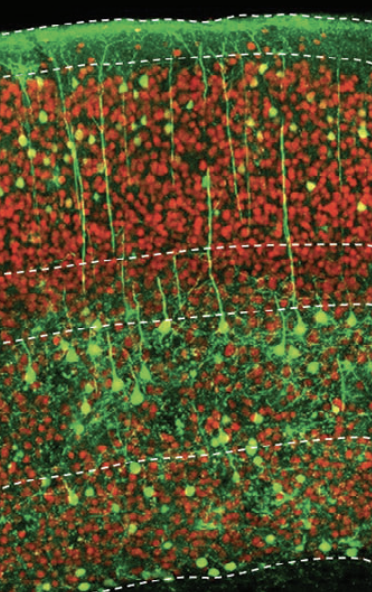

Neural tissue is composed primarily of two cell types: neurons and surrounding supportive glial cells, including astrocytes. While neurons are post-mitotic and cannot regenerate, glial cells retain the capacity to divide and proliferate. Importantly, neurons and astrocytes share a common origin from neural stem cells and exhibit overlapping molecular and functional characteristics. Leveraging this intrinsic similarity, NeuExcell has developed an in situ ATN ASTROCYTES TO NEURONS TM platform that enables the direct conversion of glial cells into neurons within diseased or injured neural tissue.

At sites of neural injury, astrocytes are abundant, making them an ideal endogenous source for neuronal regeneration. By converting these resident glial cells into functional neurons, the ATN™ platform has the potential to generate substantial numbers of new neurons, repair damaged neural tissue, and restore lost neurological function. Preclinical studies have demonstrated robust efficacy in stroke and Alzheimer's disease animal models, including neural tissue repair, mitigation of motor and cognitive deficits, and significant extension of lifespan.

NeuExcell's in situ neuroregeneration technology developed from ATN ASTROCYTES TO NEURONS (TM) platform uses AAV as a vector to locally deliver neural transcription factors to specific regions. The neurons derived from astrocytes are the correct subtypes for the target region. This technology can be used to treat various neurodegenerative diseases including common and rare diseases.